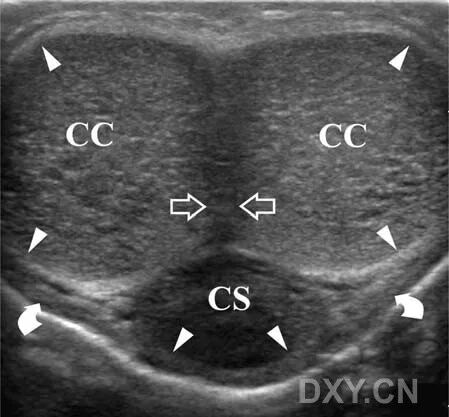

正常灰阶超声解剖。阴茎背侧轴向扫描显示成对的阴茎海绵体(CC)、尿道海绵体(CS)和阴茎隔膜(空白箭头)。白膜(短箭头)表现为围绕在海绵体外的纤细的线样回声。在邻近尿道海绵体处可看到Buck筋膜(弯曲箭头),Buck筋膜的其他部分与白膜黏贴在一起。阴茎隔膜表现为后方衰减的回声结构。

Colles’筋膜在正常人中很少能看到。白膜和Buck’s筋膜黏在一起表现为围绕在阴茎海绵体周围的线样纤细回声,勃起时会更纤细。只有当两层间出现渗液积聚或使用超高频探头时可以区分这两层不同的结构。

而血管结构可以能为分辨正常阴茎的一小部分Buck’s筋膜和下方的白膜提供一个合适的界面。

尤其是Buck’s筋膜在超声上变得可见在接近扩张的旋静脉,一个精细的线样回声表示Buck’s筋膜通常在阴茎背侧可以看到,它区分深静脉面和表浅静脉以及在接近尿道海绵体。